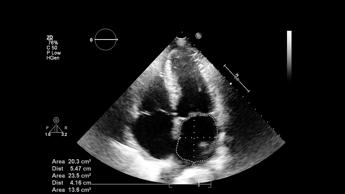

(Adnkronos) – Per la prima volta in Europa, 3 società scientifiche italiane hanno realizzato un documento pionieristico sull'ultrasonografia polmonare (Lus) nei pazienti critici, coprendo l'intero arco della vita. La 'buona pratica clinica', pubblicata il 4 novembre, nasce dalla sinergia tra la Società italiana di anestesia, analgesia, rianimazione e terapia intensiva (Siaarti), la Società italiana di radiologia medica e interventistica (Sirm) e la Società italiana di neonatologia (Sin). "Questo documento rappresenta un esempio virtuoso di collaborazione tra diverse specialità mediche – evidenzia Elena Bignami, presidente Siaarti – L'approccio innovativo adottato ottimizza l'utilizzo dell'ecografia polmonare per tutti i pazienti critici, indipendentemente dalla loro età e patologia. E' significativo come buona parte della letteratura scientifica analizzata sia di provenienza italiana, confermando il nostro Paese come front runner nel campo della ultrasonografia polmonare nel paziente critico". La rilevanza del documento emerge anche dalle parole di Giorgio Conti, Editor-in-Chief della rivista 'Jaacc' di Siaarti: "Questo documento intersocietario segna un punto di svolta nella collaborazione fra specialità mediche. Il dialogo tra anestesisti-rianimatori, radiologi, pediatri e neonatologi ha prodotto uno strumento unico, tracciando una strada innovativa da seguire anche in altri ambiti". La pubblicazione del documento – riporta una nota – sancisce un dato di fatto: l'ecografia polmonare si sta rivelando uno strumento prezioso nella pratica clinica quotidiana. "Si tratta di un documento che sottolinea l'importanza dell'ultrasonografia polmonare per migliorare la gestione clinica in ambiente ospedaliero – spiega il presidente Sirm, Andrea Giovagnoni – La Lus può ottimizzare i percorsi diagnostici, riducendo l'uso di tecniche invasive o radiologiche più costose e rischiose". Il testo "rappresenta uno strumento prezioso per decisioni cliniche rapide nelle emergenze, con l'obiettivo prioritario di salvaguardare sempre la sicurezza del paziente". "L'ecografia polmonare è una tecnica che permette di valutare le più comuni patologie polmonari tipiche dei neonati nati anche prima del termine – illustra il presidente Sin, Massimo Agosti – Consente al neonatologo di integrare il quadro clinico dei neonati critici con una metodica diagnostica efficace, rapida e facilmente riproducibile, atta ad assistere i medici nella gestione di patologie spesso rapidamente progressive e tempo dipendenti. Possiede un'alta accuratezza diagnostica, non utilizza radiazioni ionizzanti ed è facilmente adattabile al contesto della Terapia intensiva neonatale poiché eseguita dai neonatologi direttamente al letto del paziente. Pertanto, visti i suoi numerosi vantaggi, negli ultimi anni si è affermata come un insostituibile alleato in ambito neonatologico". Il documento – descrive la nota – fornisce indicazioni standardizzate per l'esecuzione degli esami ecografici, promuove la formazione continua degli operatori e definisce percorsi diagnostici basati sulle più recenti evidenze scientifiche, rappresentando un riferimento fondamentale per il miglioramento della pratica clinica in Italia. "L'ecografia polmonare riduce i rischi per il paziente e accorcia i tempi diagnostici, aumentando la precisione e l'efficacia delle cure, soprattutto nei casi di emergenza", rimarcano gli esperti. Grazie a questo documento, l'Italia si pone all'avanguardia in Europa per l'uso clinico di questa tecnica, offrendo uno standard di cura innovativo e di alta qualità. —salutewebinfo@adnkronos.com (Web Info)